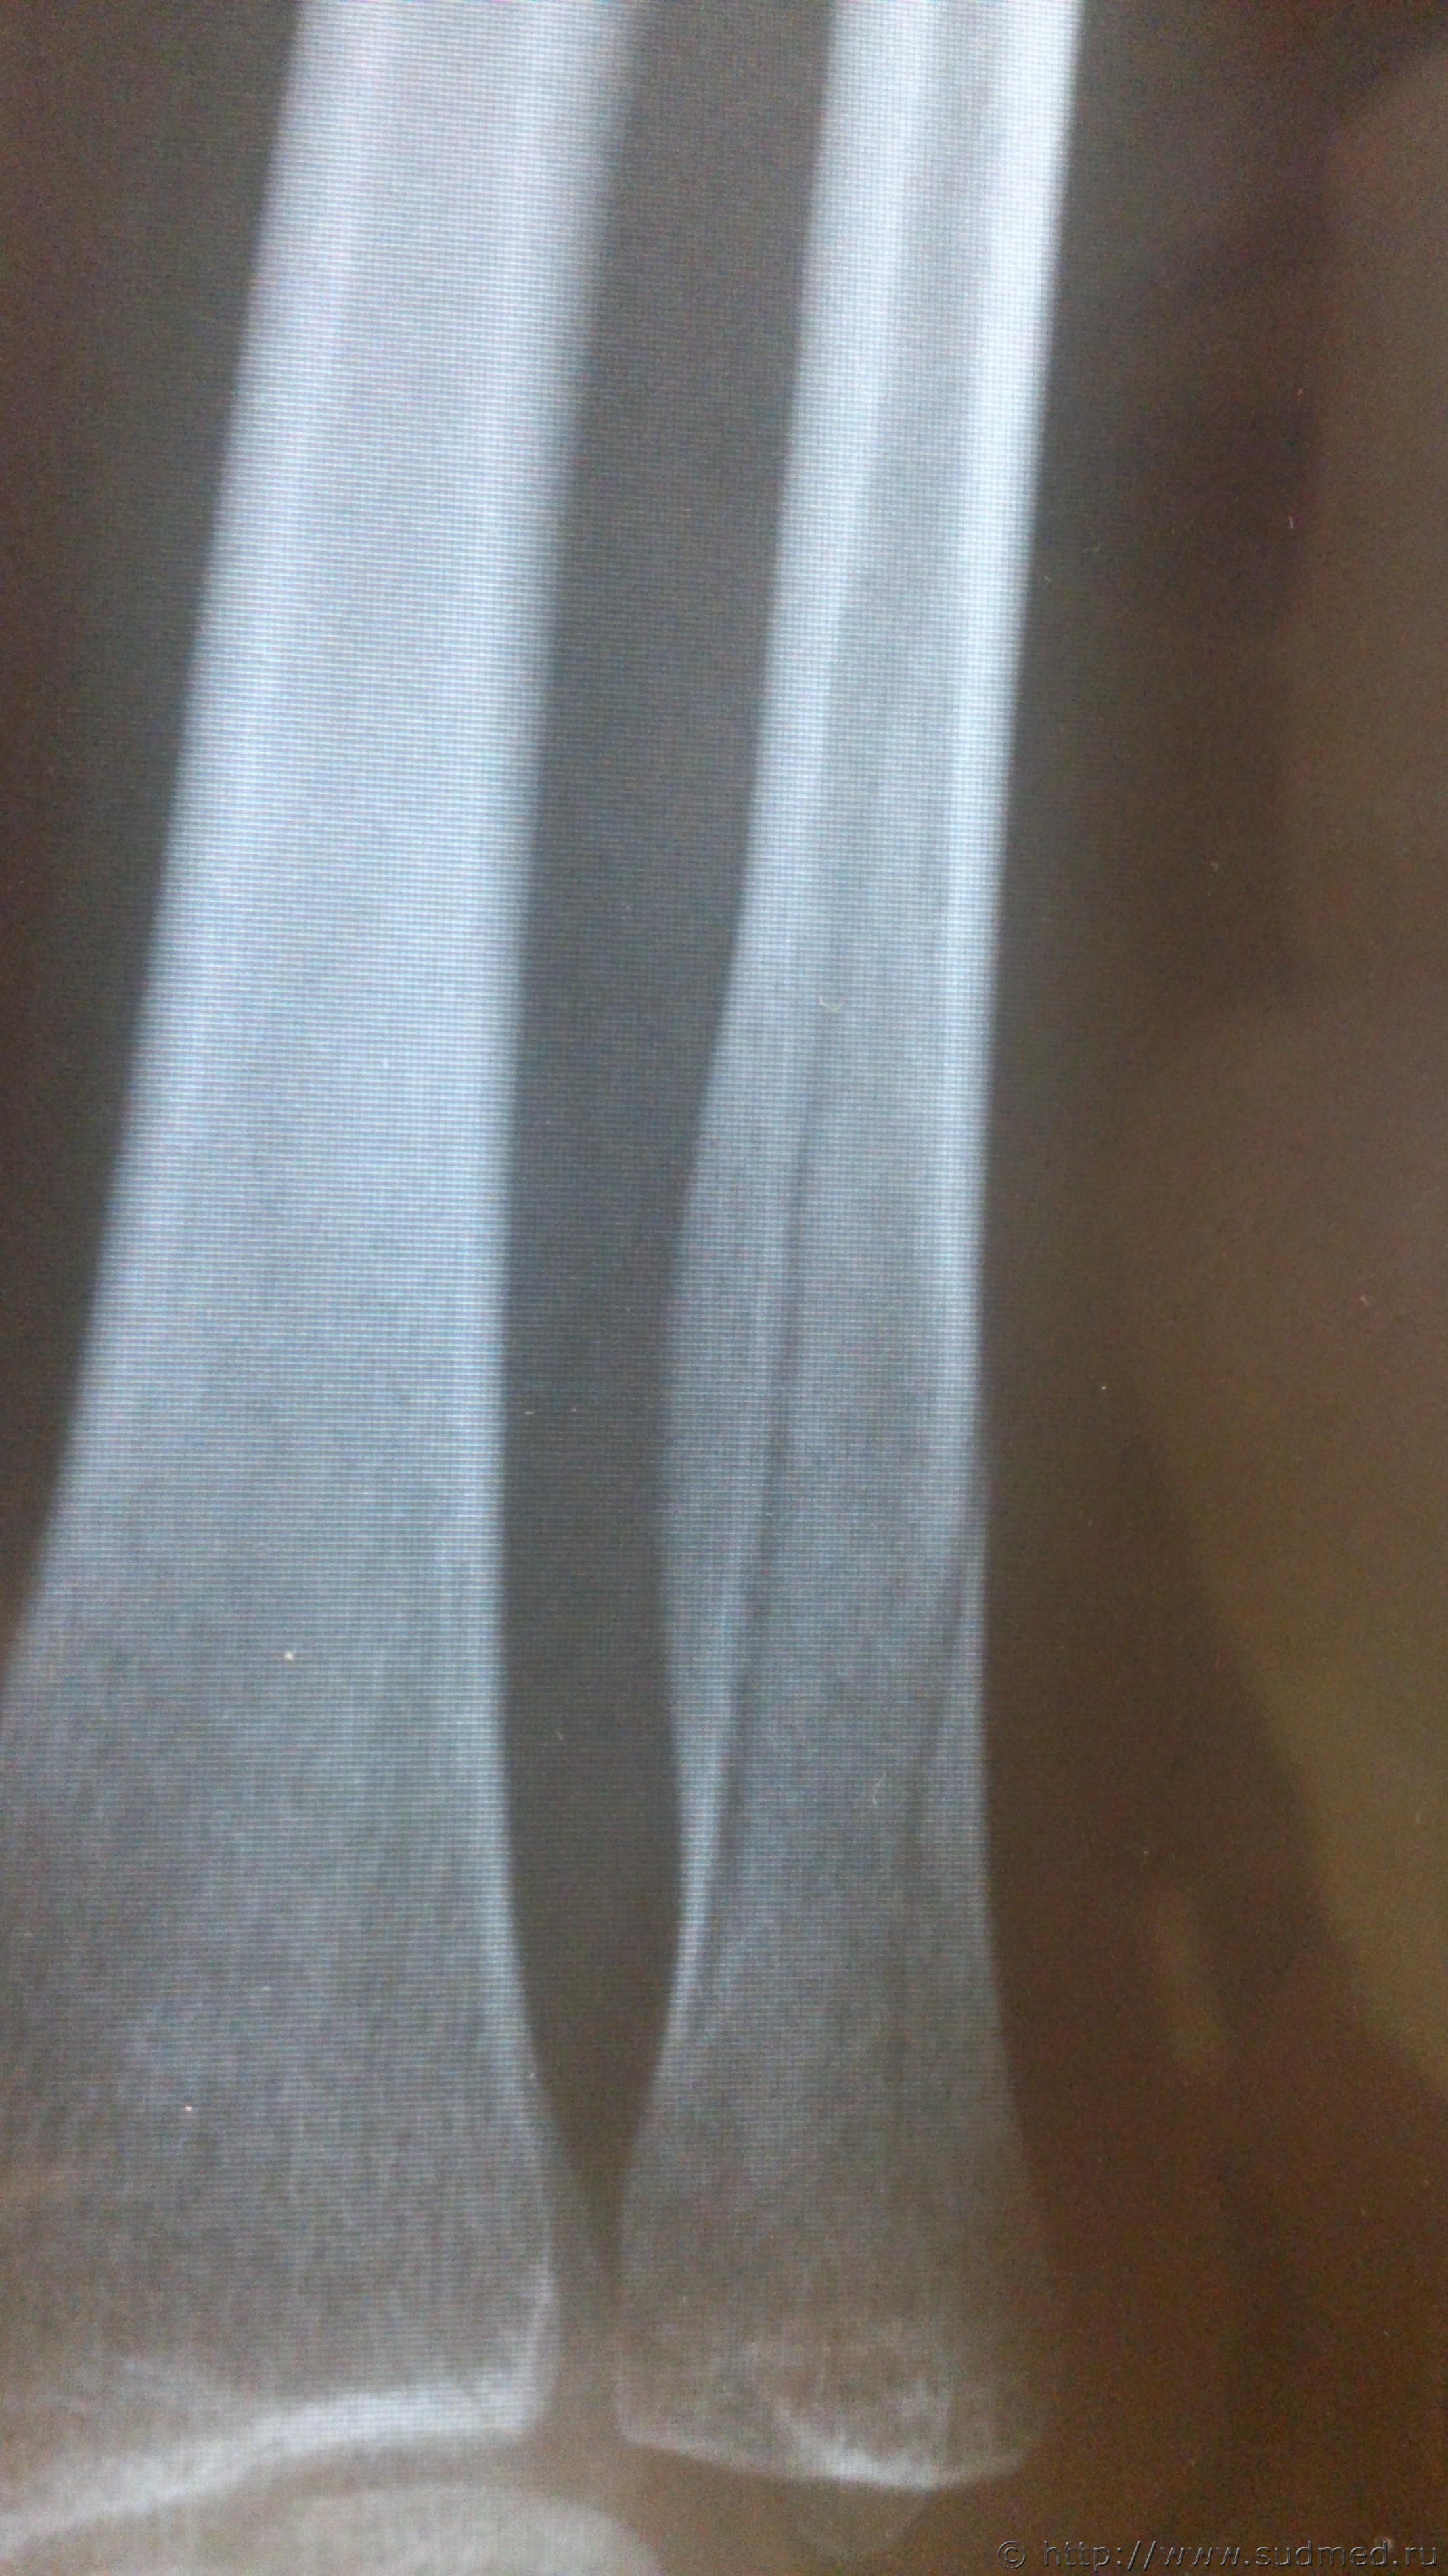

Здравствуйте, уважаемые коллеги! Возник вопрос по механизму образования перелома локтевой кости. Согласно описанию рентгенолога: «в нижней трети правой локтевой кости определяются два линейных просветления, направленных параллельно оси кости, шириной около 2,0 мм, с достаточно четкими контурами, без деформации оси кости, без видимой динамики рентгенологической картины между исследованиями (от 01.09.16 и от 07.10.16) – признаки консолидации не выявляются (отсутствует уплотнение костной структуры, костная мозоль не формируется)» Выводы: установлены признаки вертикального перелома правой локтевой кости в нижней трети без смещения отломков. Диагноз травмпункта: «Закрытый перелом ДМЭ правой локтевой кости со смещением отломков». По обстоятельствам - «нанес один удар деревянным стулом сверху-вниз, защищаясь от удара, лежа на кровати, подставила свою правую руку». Встречался ли кто-нибудь с такого рода переломами и есть ли соображения относительно механизма его образования.

Эскизы прикрепленных изображений

Судебная медицина - Прикрепленное изображение Судебная медицина - Прикрепленное изображение Судебная медицина - Прикрепленное изображение Судебная медицина - Прикрепленное изображение